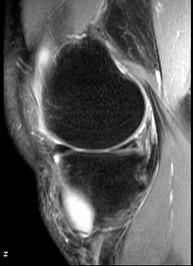

问题 男,21岁,膝关节疼痛,行走困难,曾有外伤史,请结合所提供的图像,选择最佳选项 ( )

选项 A、未见异常 B、前十字韧带撕裂与巨大半月板囊肿 C、内侧半月板撕裂 D、巨大半月板囊肿 E、内侧半月板撕裂与巨大半月板囊肿

答案 E